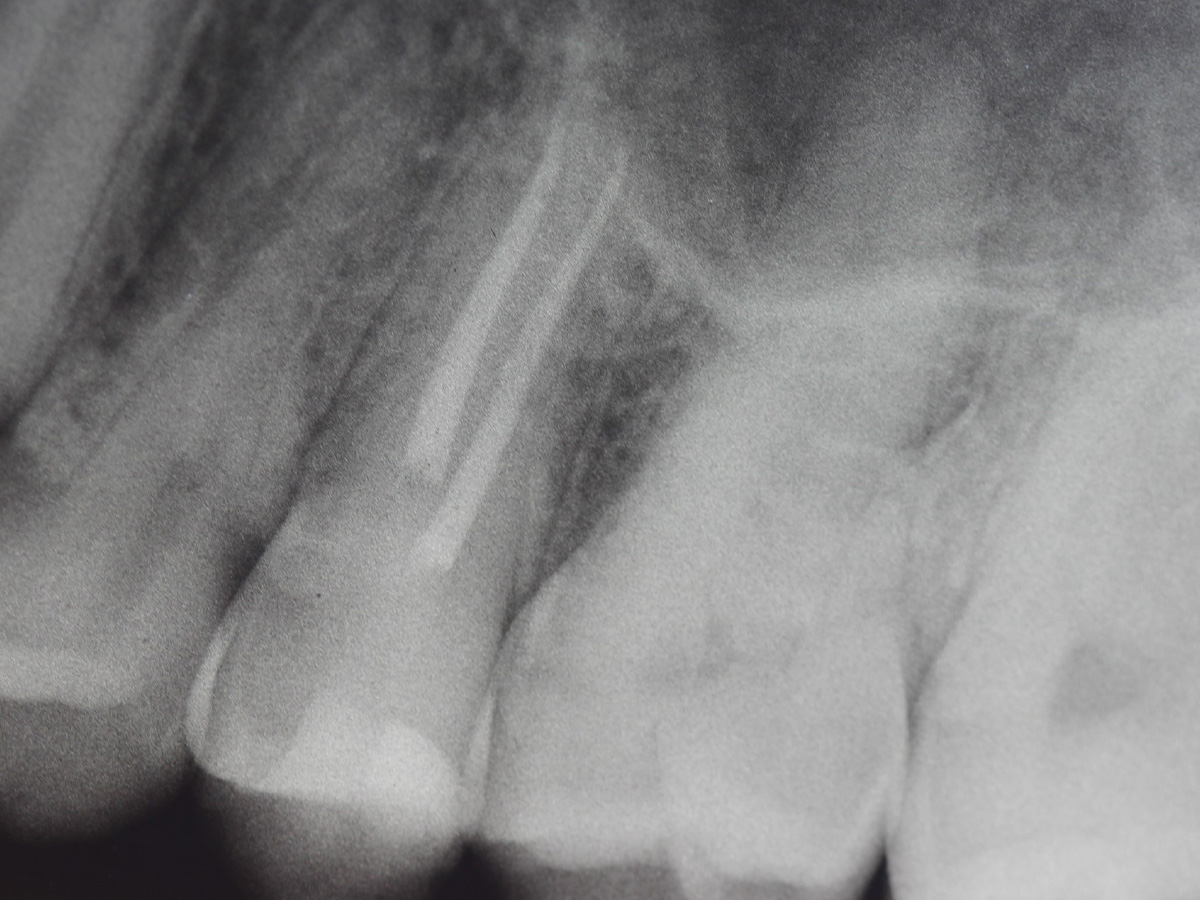

Abbildung 27

Kontrollröntgenaufnahme